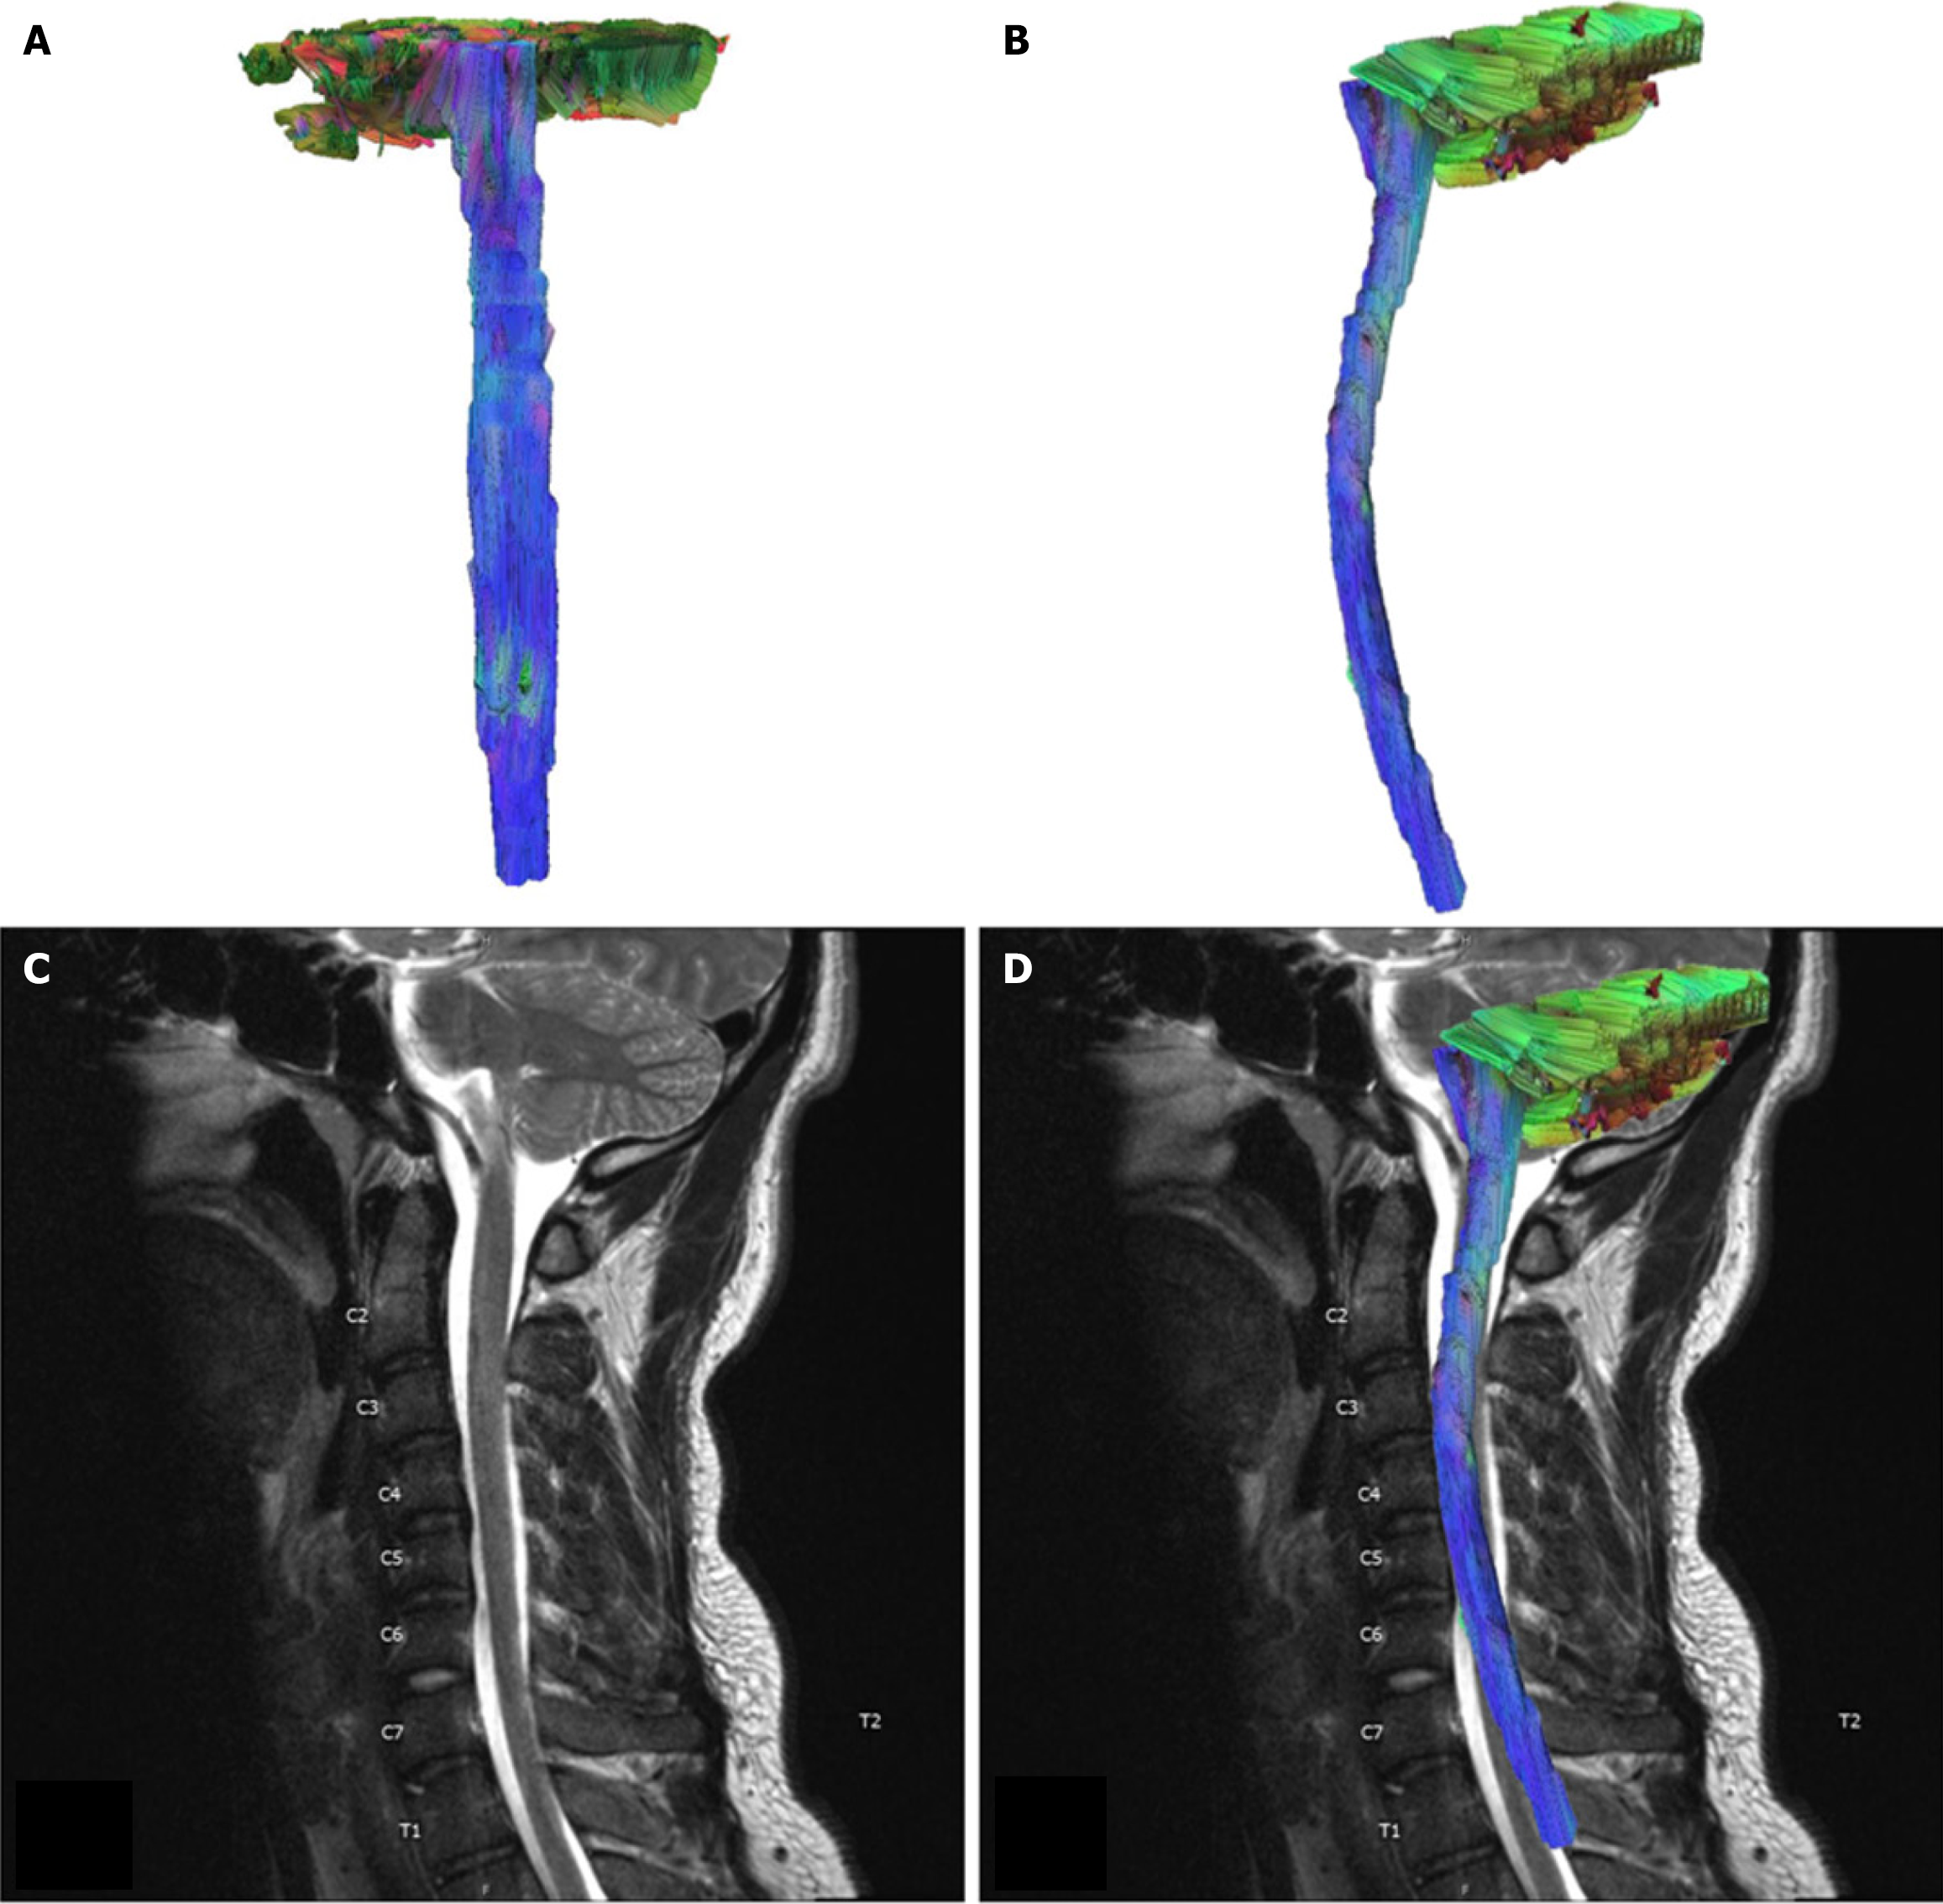

Figure 1 Control case.

A: AP view of tractography model of a 22 year old male control case; B: Sagittal view of the tractography model; C: T2-weighted Sagittal view of the cervical spinal cord. No discernable signal abnormality in the cervical spinal cord; D: Tractography of control case superimposed over T2-weighted sagittal view of the cervical spinal cord.